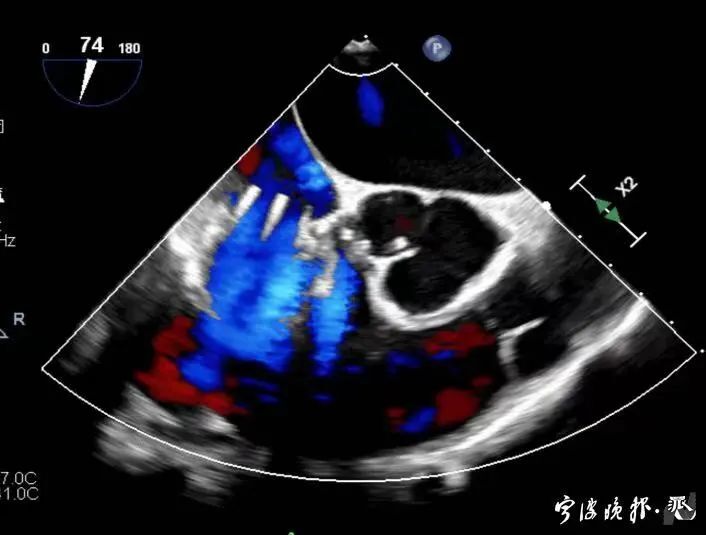

術(shù)后食道心超示三尖瓣反流消失

得知可以微創(chuàng)手術(shù),陳大爺一家決定放手一搏。寧波市醫(yī)療中心李惠利醫(yī)院心臟瓣膜中心團(tuán)隊(duì)反復(fù)就術(shù)前準(zhǔn)備、手術(shù)步驟及術(shù)后可能出現(xiàn)的各種情況做了預(yù)案。3月4日,陳大爺?shù)氖中g(shù)成功進(jìn)行,術(shù)中得到LuX-Valve經(jīng)導(dǎo)管三尖瓣置換術(shù)原創(chuàng)團(tuán)隊(duì),上海長海醫(yī)院陸方林主任團(tuán)隊(duì)的鼎力支持,術(shù)后陳大爺?shù)男呐K三尖瓣反流立即消失。術(shù)后瓣膜中心CCU(心臟監(jiān)護(hù))團(tuán)隊(duì)和心內(nèi)科團(tuán)隊(duì)迎接一個又一個右心瓣膜置換后的血流動力學(xué)改變等帶來的挑戰(zhàn),克服種種難關(guān),二周后患者進(jìn)入早期心臟康復(fù)。目前陳大爺已經(jīng)順利出院,沒有胸悶氣急,生活自理,精神狀態(tài)也很好,瓣膜中心團(tuán)隊(duì)也在對他持續(xù)隨訪中。